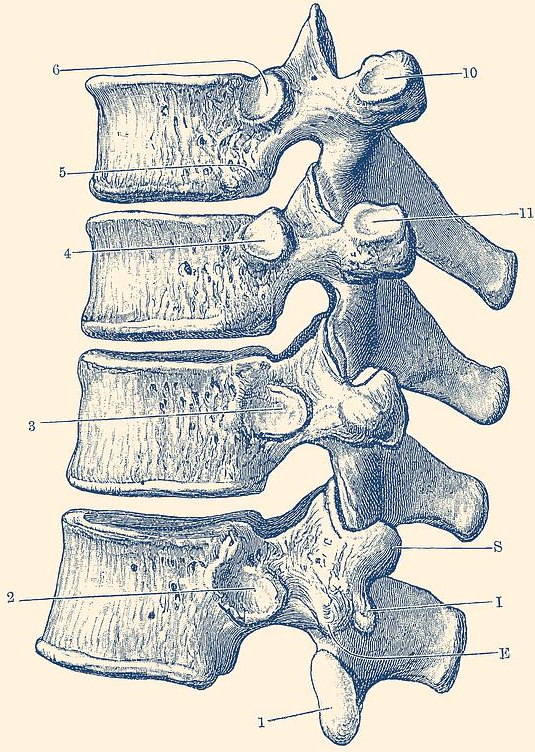

Spinal cord anatomy

Day twenty-nine, wow does time fly! We have over four weeks worth of fun spinal knowledge for you to tap into, all in reverse chronological order in our handy neuroanatomy category! If you read the title, you know we’re back on tract (see what I did there?). Today we’re talking the spino-olivary tract, or is it the olivospinal tract? Keep reading to find out!